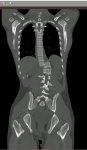

Здравствуй двачик, на прошлой неделе вышел из отпуска и уже дергается глазик, вчера сидел на работке пока поликлинику не закрыли и не все доделал. Не могу перестать кричать внутри головы! Потому мы с вами будем сегодня играть в доктора! Я буду вам показывать фоточки а вы угадывать пиздецомы! Што шпогнали! Найдите поломку!